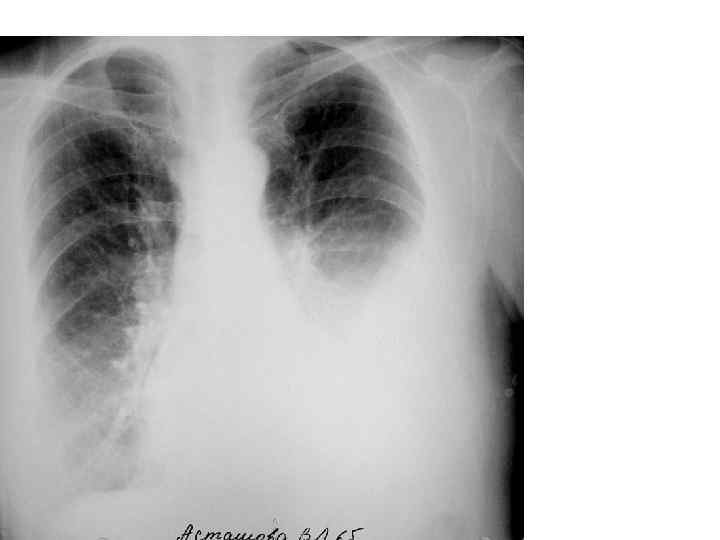

ГИДРОТОРАКС СПРАВА

ЭМПИЕМА ПЛЕВРЫ СЛЕВА